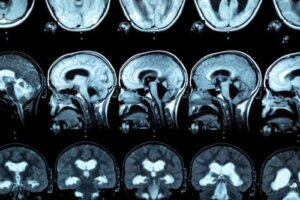

Forstørrelse af hjernebjælken kan også konstateres, hvis der laves et hjernebillede. I nogle tilfælde kan der være tegn på interhemisfærisk afbrydelsessyndrom.

Til diagnosticering af denne sygdom udføres en MR-scanning, så læsioner i hjernebjælken observeres. I denne henseende viser forskning, at personer med alkoholforstyrrelse viser en reduktion i den forreste, midterste og bageste tykkelse af hjernebjælken samt variationer i størrelsen af frontallappen og kortikale sulci.